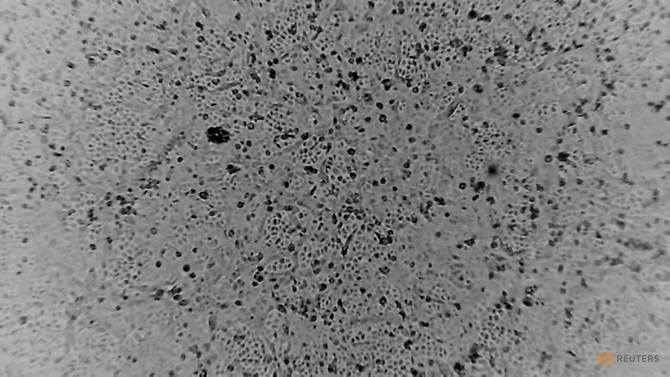

Virus Corona 2019-nCov đang phát triển trong các tế bào Vero E6. Ảnh: Reuters